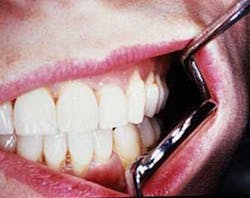

Constriction of oral tissues; patient with microstomia. Courtesy of Dr. T.D. Rees

Perioral and intraoral characteristics: Depending upon the extent of the disorder, the patient may exhibit constriction of the mouth (microstomia) and an inability to close the lips, due to the amount of fibrosis (see Figures 1 and 2). In Figure 1, a band of thick fibrotic tissue is evident on the lip extending to the wet line of the lip. In Figure 2, the skin and oral tissues are tight even with the aid of mirrors. Leader5 suggests a physical therapy technique used to increase the mouth opening over time: Lubricate the mouth, have the patient cross arms at chest height, with palms facing down, and use the thumbs to stretch the corners of the mouth for several minutes. Over time, the tissue may become more flexible. TMJ problems may be pronounced due to tissue constriction.